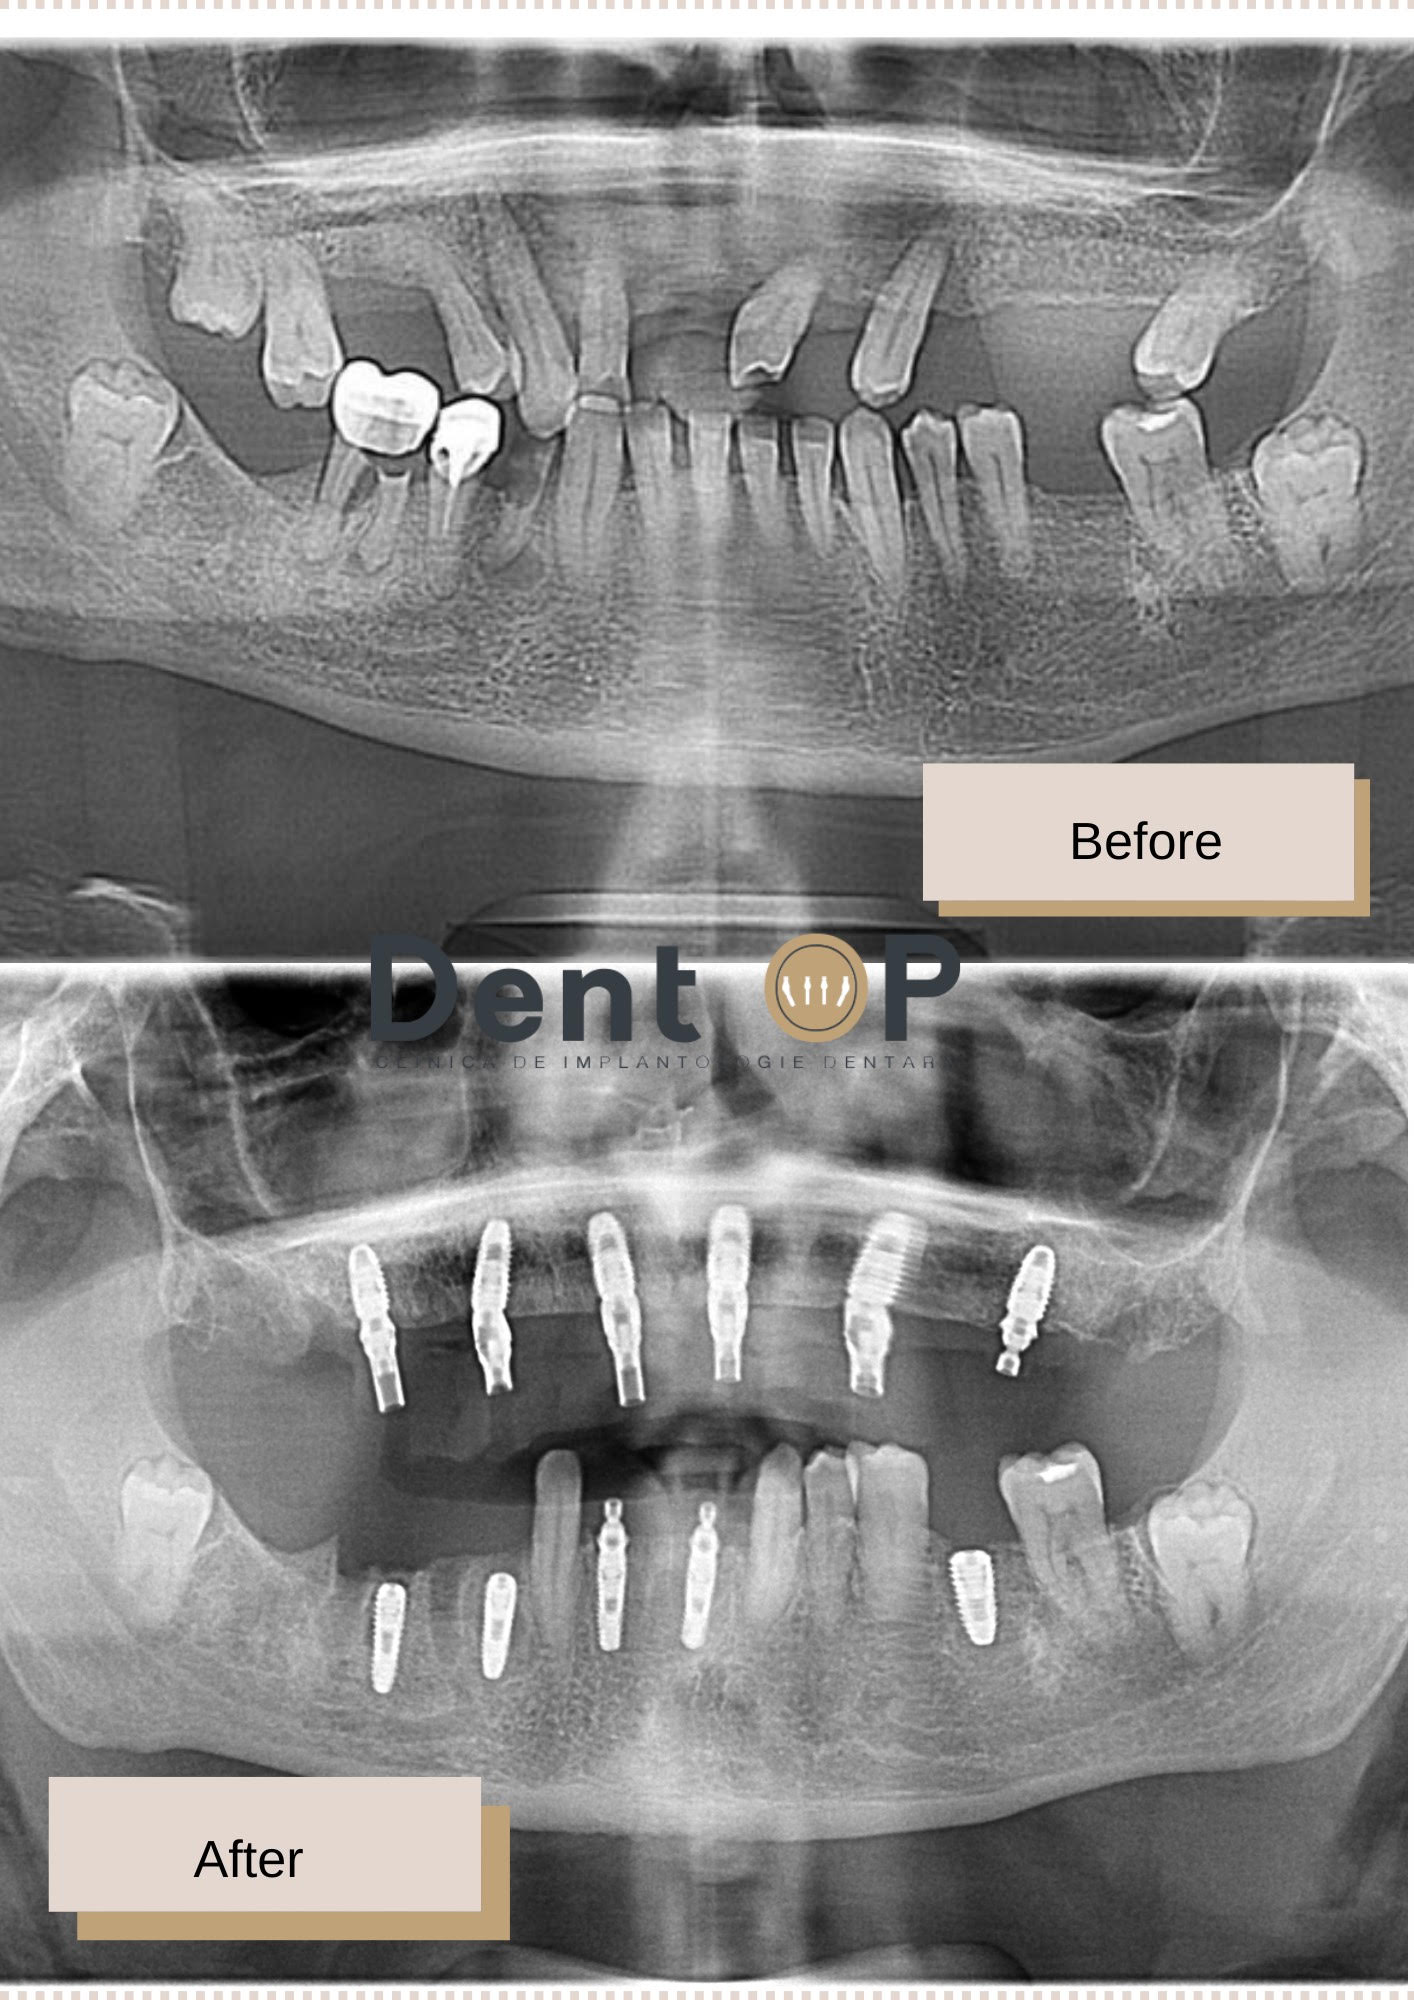

În cadrul consultației cu Dr Cazacu Corrado i s-a comunicat un plan de tratament cu 11 implanturi dentare – 6 la maxilar și 5 la mandibulă. În următoarele 24h, pacientul a primit și lucrările provizorii pe care le-a purtat timp de 6 luni.

După o serie de probe, s-au inserat și lucrările finale cu un aspect plăcut, estetic.